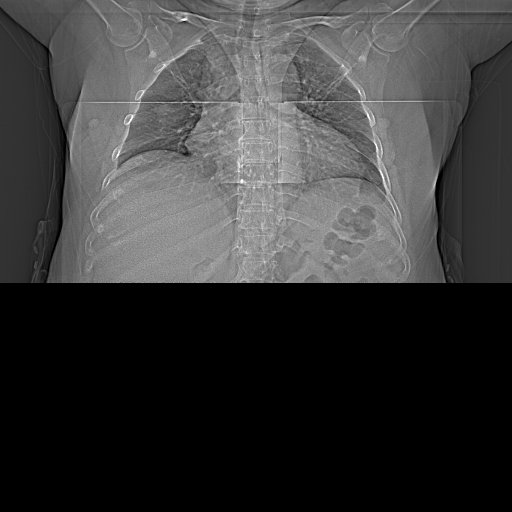

患者,女,53.近一月感觉胸痛,气短,乏力,腰痛,夜间口干。

右肺上叶后段见不规则结节影,边缘欠清楚,且见胸膜册陷征,左肺胸膜下见小结节影,纵膈见淋大淋巴结影,肝内见多发类圆形低密度影,考虑:右上肺周围性肺癌伴淋巴结转移可能性大,左上肺胸膜下结节,不排除转移,肝囊肿。

右下肺可见外形不规则结节,且见胸膜凹陷征,左上肺胸膜下小结节,纵膈内可见肿大淋巴结,肝实质弥散减低,肝顶部可见多个圆形低密度影。考虑:右下肺占位---周围型肺癌伴纵隔淋巴结转移可能性大,左上肺胸膜下结节,不排除转移,肝内低密度影,考虑囊肿可能性大。提示脂肪肝。

1)考虑右肺上叶后段周围型肺癌并纵隔淋巴结转移。2)左上胸膜下小结节灶,不排除转移。3)肝脏多发类圆形低密度影,考虑肝囊肿

1)考虑右肺上叶后段周围型肺癌并纵隔淋巴结转移。2)左上胸膜下小结节灶,不排除转移。3)肝脏多发类圆形低密度影,考虑肝囊肿。